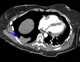

Lobar torsion